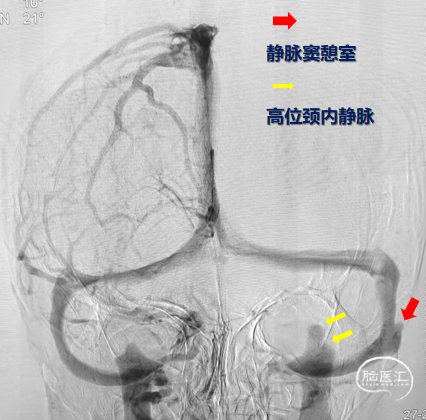

红色箭头示静脉窦憩室

➤DSA

乙状窦憩室

静脉窦狭窄

使用双导管继续在Xpert Pro支架辅助下进行弹簧圈填塞,再次造影显示:憩室内血液已完全阻滞,未见显影。

Xpert Pro支架在乙状窦内形态良好。静脉窦憩室闭塞完全。